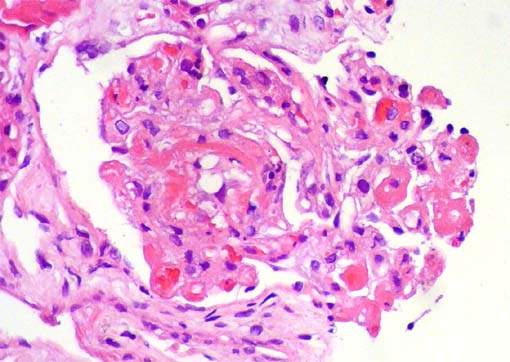

[TEČAJ I. KATEGORIJE] Primarne i sekundarne bolesti glomerula

Program i prijavnica